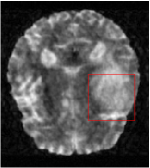

Qualitative comparison between conventional and Meta-learning methods are shown in Figure 1 and 3, which display the reconstructed MR images of the same slice for T1 and T2 respectively, we label the zoomed-in details of HGG in the red boxes. We observe the evidence that conventional learning is more blurry and lost sharp edges, especially in lower CS ratios. From the point-wise error map, we find meta-learning has the ability to reduce noises especially in some detailed and complicated regions comparing to conventional learning.

In this section, we test the generalizability of the proposed model that tests on unseen tasks. We fix the well-trained task-invariant parameter and only train for sampling ratios 15%, 25% and 35% with radio masks and sampling ratios 10%, 20%, 30% and 40% with Cartesian masks. In this experiment, we only used 100 training data for each CS ratio and apply a total of 50 epochs. The averaged evaluation values and standard deviations are listed in Table 5.4 and 5.4 for reconstructed T1 and T2 brain images respectively that proceed with radio masks, and Table 5.4 shows the qualitative performance for reconstructed T2 brain image that applied random Cartesian sampling masks. In T1 image reconstruction results, meta-learning improved 1.6921 dB in PSNR for 15% CS ratio, 1.6608 dB for 25% CS ratio, and 0.5764 dB for 35% comparing to the conventional method, which in the tendency that the level of reconstruction quality for lower CS ratios improved more than higher CS ratios. A similar trend happens in T2 reconstruction results with different sampling masks. The qualitative comparisons are illustrated in Figure 2, 4 and 5 for T1 and T2 images tested in skewed CS ratios in radio masks, and T2 images tested in Cartesian masks with regular CS ratios respectively. In the experiments that conducted with radio masks, meta-learning is superior to conventional learning especially at CS ratio 15%, one can observe that the detailed region in red boxes keeps edges and is more close to the true image, while conventional method reconstructions are hazier and lost details in some complicated tissue. The point-wise error map also indicates that Meta-learning has the ability to suppress noises.